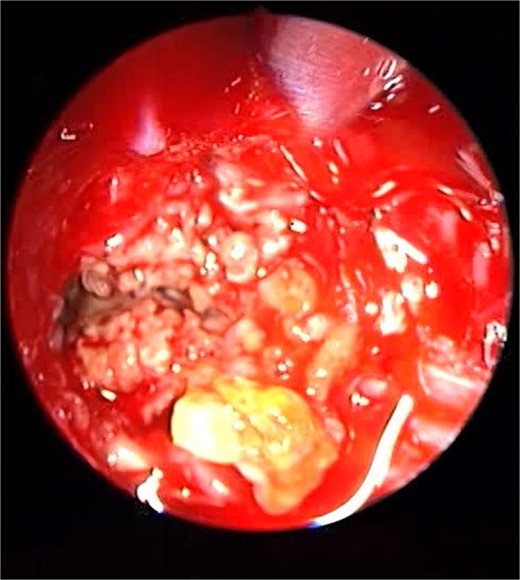

Endoscopic intraoperative image of the sphenoid sinus post removal of the fungal mud and mucin from the lateral wall of the sphenoid sinus.

Patient presented to the emergency department with four days history of sever left side headache associated with nausea and vomiting, and nasal discharge with on\off nasal obstruction. Two days history of diplopia with lateral gaze of the left eye, with decrease the visual acuity. Ophthalmologic examination revealed left abducens nerve palsy. Other neurologic examinations were within normal. Endoscopic nasal examination revealed left multiple grade two nasal polyps occupying the middle meatus. Pre-operative brain computed tomography (CT) shows bilateral near total opacification and expansion of the paranasal sinuses and nasal cavity (Fig. 1). Additionally, there is evidence of invasion of the left cavernous sinus with encasement of cavernous segment of left internal carotid artery (ICA). Furthermore, pituitary gland and optic chiasm displaced superiorly. Magnetic resonance imaging revealed that the sphenoid sinus is expanded and bulging superiorly into the pituitary fossa causing displacement of pituitary gland and stalk without mass effect upon the optic chiasm (Fig. 2). It extends laterally causing effacement of the cavernous sinus and left Meckel’s cave. No evidence of intracranial extension. The patient underwent functional endoscopic sinus surgery with computer-assisted navigation system. Intraoperatively, sphenoid sinus was full of fungal mud and mucin (Fig. 3). The polyps were removed completely from the nasal cavities, fungal mud, and mucin were removed from the sinuses (Figs 4 and 5). Patient had dramatic improvement after surgery, the rhinosinusitis symptoms are resolved, the diplopia has been improved, and the paranasal sinuses were clear. The patient was discharged with topical corticosteroid and saline irrigations.